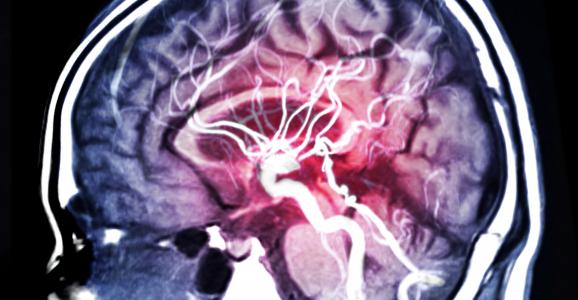

COGNITION : Pourquoi diabète et AVC forment un cocktail particulièrement mauvais

Un diabète de type 2 préexistant est lié à de moins bonnes performances cognitives après un accident vasculaire cérébral (AVC), soulignent ces chercheurs de l’Université de Nouvelle-Galles du Sud (Australie). Ces travaux, présentés dans Stroke, une revue de l’American Heart Association, confirment des preuves déjà solides d’une association entre le diabète de type 2 et une déficience cognitive, alertent à vérifier la capacité du patient, post-AVC, à contrôler son diabète et incitent à détecter les premiers signes de prédiabète afin d‘éviter ou de retarder ces complications cérébrales et cognitives.

Ainsi, les personnes atteintes de diabète de type 2 présentent de moins bonnes performances cognitives 3 à 6 mois après un AVC, par rapport à des patients non diabétiques. Au-delà relation entre diabète et cognition est complexe : le diabète de type 2 augmente le risque d’AVC et a déjà été associé à des troubles cognitifs ainsi qu’à un risque plus élevé de démence.